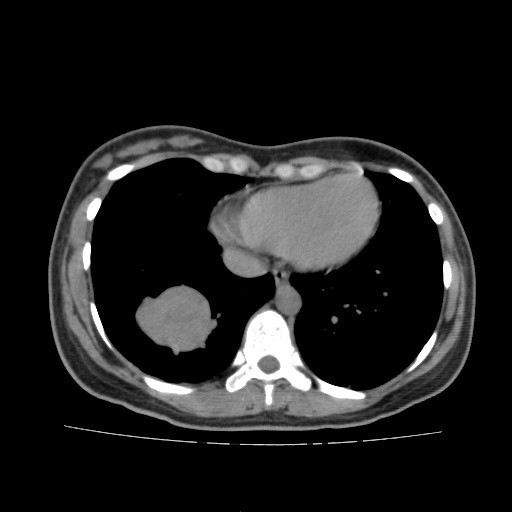

查体:右大腿上段较左侧增粗,后内侧皮下可触及大小约5*6cm肿物,质软,边界不清,活动度可,压痛(+),无波动感。 辅助检查:胸部CT:双肺多发转移瘤。

诊断:肺占位性病变(转移瘤?);大腿软组织疾患(右侧大腿肿物) 治疗:入院右下肢MR平扫+增强扫描:右侧大收肌软组织占位性病变,考虑间叶源性恶性肿瘤可能性大,血管源性可能?瘤周多发静脉曲张及侧枝循环形成,建议CT增强扫描进一步检查明确血管情况。遂于声引导下右大腿肿物穿刺活检,病理结果提示:(右大腿肿物)送检穿刺组织,肿瘤细胞形成器官样及腺泡状结构,细胞巢间为纤维性分隔,细胞呈大圆形、多边形,胞质丰富透亮,部分呈嗜伊红色,细胞核大,核分裂象少见,结合临床病史及免疫组化,考虑为腺泡状软组织肉瘤。免疫组化结果(①):CK(-),Vim(-),Ki-67(5%+),HMB45(-),MelanA(-),SMA(+),desmin(-),Myogenin(-),MyoD1(-),S100(-),NSE(部分+),CD56(-)。